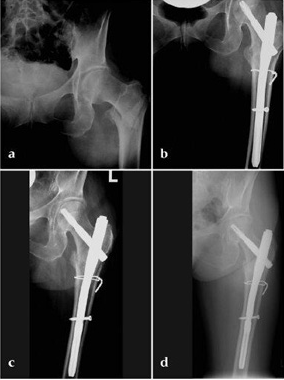

Case 1:

47-year-old female, slipped and fell down the stairs. Traumatic, single 31-A2.1 fracture treated with PFNA.